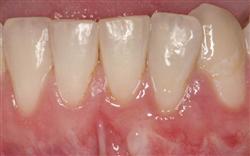

Cosmetic Soft Tissue Grafting

In addition to the functional problems previously mentioned, receding gums can look unsightly.

Longer looking teeth and exposed tooth roots give an "old" appearance to your smile. Some people cover their mouths when they smile for this very reason.

Cosmetic Soft Tissue Grafting can add a new youthful appearance to your smile. In your initial consultation with Dr. Hoidal, he will thoroughly explain what can be achieved in your particular case.